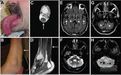

影像學檢查腦部核磁共振可能發現齒狀核(dentatenuclei)及小腦、大腦白質的異常